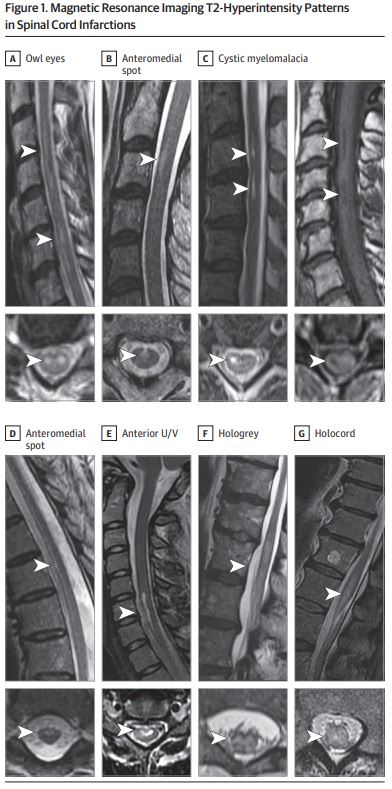

Other common T2-hyperintense patterns are highlighted well in @nzalewski2's paper as shown below.